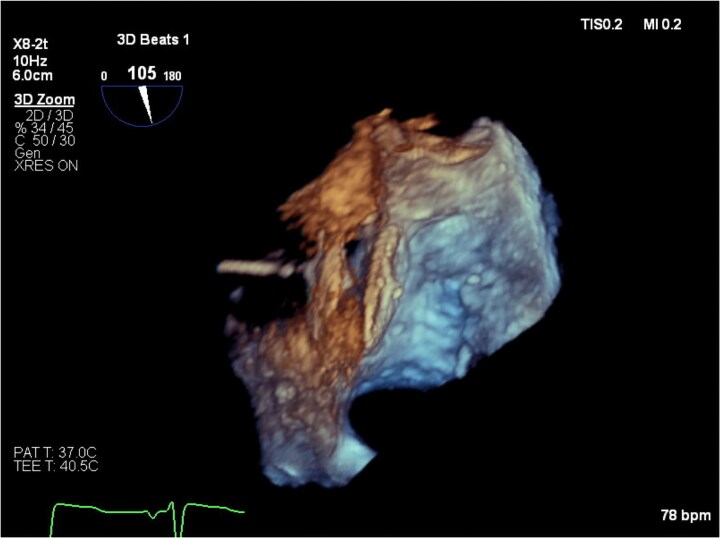

Case summary: A 77-year-old patient with severe aortic stenosis was referred for TAVI at our institution. On transthoracic echocardiography, dilatation of the ascending aorta (40 mm) and a mobile atrial septal aneurysm (ASA) were noted. Transcatheter aortic valve implantation was complicated by annular rupture and aortic intramural haematoma (IMH), managed conservatively. Three weeks after discharge, the patient re-presented with cholecystitis and underwent cholecystectomy. Post-operatively, marked hypoxaemia was noted during orthostasis. Transthoracic echocardiography showed the ASA bulging into the left atrium, with a strongly positive saline contrast study while upright. A PFO was identified on transoesophageal echocardiography and successfully percutaneously closed, with hypoxaemia resolving.